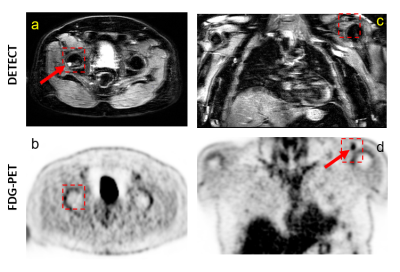

Figure 3. Representative images of WBMRI-DETECT (a, c) and FDG-PET (b, d) are shown in a 62-year-old subject where lesions appear on one modality, but not the other. (a-b) show an axial view of the pelvis where a lesion is visible DETECT (a) in the femur (red arrow), but not in the same region for FDG-PET (b). (c-d) show a coronal view of the chest where a lesion is seen in FDG-PET (d) in the AC joint (red arrow), but not in DETECT (c). However, in subjects where both FDG-PET and WBMRI have been clinically evaluated, WBMRI uniquely identified 10 lesions, and FDG-PET uniquely identified 4 lesions.